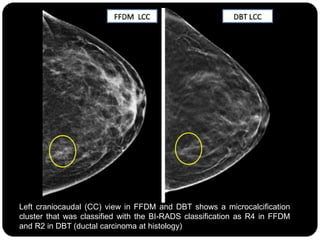

Left craniocaudal (CC) view in FFDM and DBT shows a microcalcification

cluster that was classified with the BI-RADS classification as R4 in FFDM

and R2 in DBT (ductal carcinoma at histology)